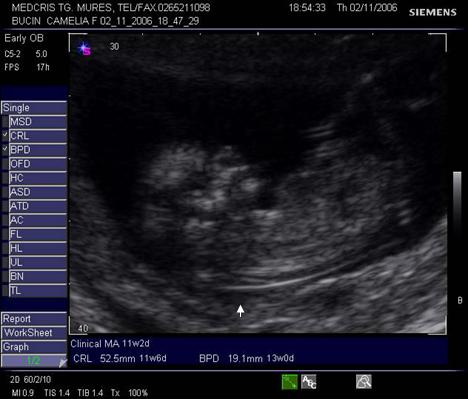

Fig nr. 12. Embrion corespunzator la 6 sapt si 3 zile

( masurat intre cele doua calipere )